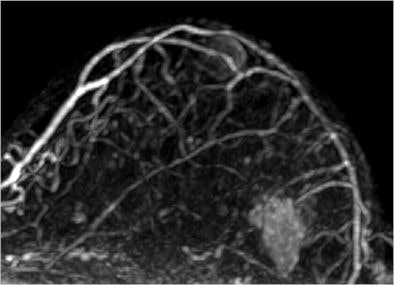

| Image is of a 50-year-old woman with a family history of breast cancer. The patient received MRI following inconclusive mammography and ultrasound findings. Evaluation of images in matched pairs confirmed unanimous reader preference for gadobenate dimeglumine for lesion conspicuity, border delineation, and overall diagnostic performance. Image courtesy of Radiology. |